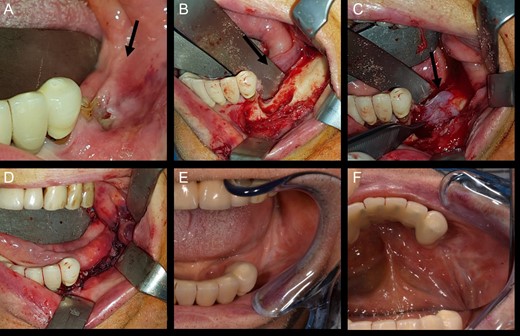

In November 2016, the patient underwent surgery under general anaesthesia. After infiltration of a local anaesthetic (mepivacaine + adrenaline 1:200 000), surgery was carried out as described: mucoperiosteal incision of the right mandible with mesial and distal drainage, extensive fistulectomy of the hyperplastic mucose membrane, which showed multiple fistulas, skeletonisation and exposure of abundant necrotic tissue; debridement of hyperplastic-inflammatory tissue and ostectomy of necrotic bone with osteoplasty of sharp edges; positioning of HAM and water and hermetic suture with Polisorb 3/0 absorbable braided thread (Fig. 2A–E). Histological examination confirmed the presence of inflammation and the diagnosis of osteonecrosis. The mesial and distal bone curettage margins were dictated by the x-ray images (Fig. 3) identifying above all the radio-opaque areas, often associated with a periosteal reaction, as well as by the need to remove any bone sequestra present. The imaging was also associated with the intraoperative assessment of the macroscopic appearance of the bone and in particular the signs of bleeding from the cortex and medulla. The HAM was 3 × 3 cm2 in size and was positioned over the curetted area and under the mucosal flap.

View of mandibular alveolar process in patient 1: (A) preoperative BRONJ affected area; (B) fistula, (C) curetted area, (D) HAM application, (E) suture of mucosal soft tissues and (F) postoperative follow-up after a period of 180 days.

The patient was submitted to a clinical and radiological follow-up 180 days after the procedure. The intraoral wound was completely sealed, the patient was asymptomatic and no further abscesses had developed (Fig. 2F).